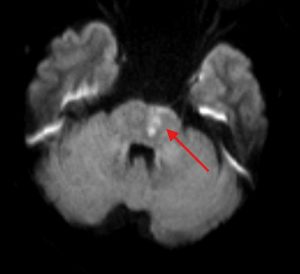

Hình ảnh tổn thương nhồi máu cầu não trái trên phim MRI của bệnh nhân đột quỵ